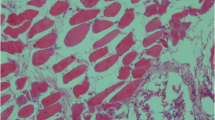

Postmortem findings on 8 out of 30 infected animals showed different PM lesions (Table 1). C. perfringens was recovered from lung samples of only six cases. Briefly, on blood base agar with 7% sterile blood, C. perfringens colonies were 2–3 mm in diameter, rounded, raised, glistened, and showed double zone of hemolysis. On TSC agar, C. perfringens colonies were black in color. Microscopically, C. perfringens isolates appeared to be Gram-positive short plumb bacilli rarely having central oval non-bulging endospores. Biochemical tests were confirmative to C. perfringens, while multiplex PCR revealed presence of C. perfringens alpha toxin gene (Fig. 1).

Multiplex PCR of the C. perfringens enterotoxin (CPE) plc gene in the lung tissue of C. perfringens-infected cattle and buffalo. PC, positive control; NC, negative control; Lg, lung; a, alpha; b, beta; e, epsilon; and I, iota toxins of C. perfringens; M indicates a 100-bp DNA ladder. The expected size of the PCR product was 402 bp, 236 bp, 541 bp, and 317 bp for alpha, beta, epsilon, and iota toxins of C. perfringens, respectively